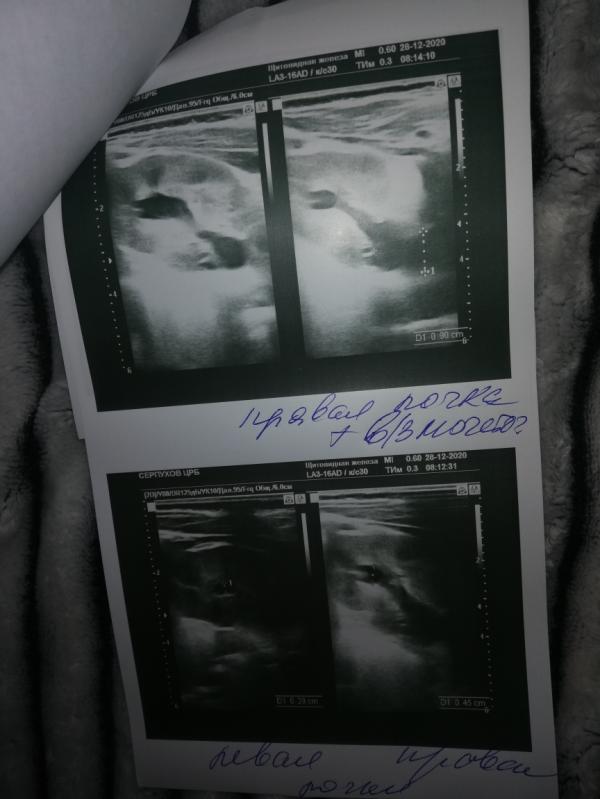

Девочки помогите пожалуйста может у кого то такое было. Сегодня были на узи почек и надпочечников планово (нам почти 2 месяца) сказали что разширен канал мочеточника, и и увеличена что-то в почке вроде как (почерк не понятен) сказали что это врождённое, типо должны были на скрининги сказать. Хотя я делала все скрининги + платно наблюдалась и планово. Никто ничего не увидел в утробе. Завтра пойду на платное узи. Может всё таки не правильно увидела....

Прежде чем ехать к нефролог в Москву, решила ещё раз сходить на узи. Так как девушка которая делала нам узи сказала что должны били сказать на скрининге об этом. Но я была у 4х врачей разных делала узи и не кто не увидел каких либо отклонений. И именно почки тоже смотрели когда была на 36-37 вроде недели. Точно уже не помню

Дело в том что у нас в городе нет детских нефрологов (к нему направили) говорят надо ехать в Москву только. Говорят не критично, но и не есть норма((((